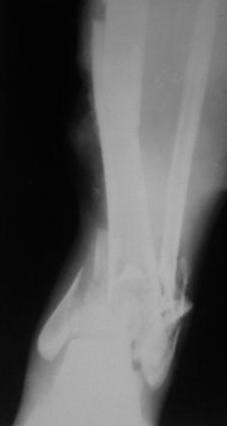

Открытый перелом 43.С3.3

Больной 41г переведен из ЦРБ, травма в результате ДТП- 5 дней назад, произведена ПХО раны, наложена гипсовая повязка.

1. ПХО произведена в ЦРБ, поэтому по имеюшимися данным ( клиника, Р-графия, допплер обследования) примерно можно так сформулировать; 43.С3.3/I03-MT3-NV1.